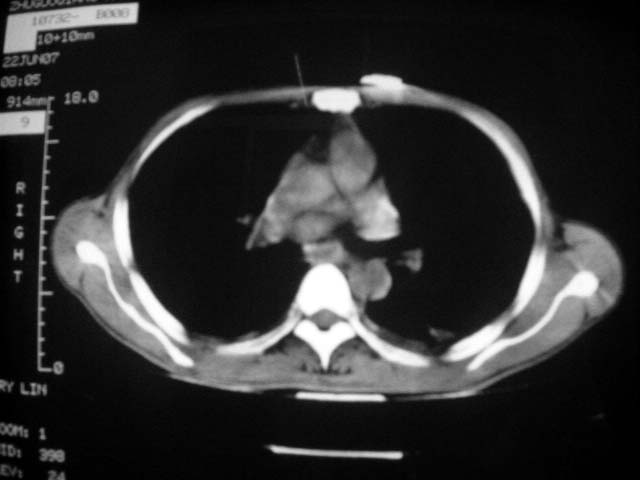

标题: CT7988D:近期图像 出乎意料!

从ct7988c 至今未用任何抗生素及抗痨药,维持保肝治疗。患者低热、咳血渐消失。

07年6月22号复查

前几次大家认为是转移癌,但此次复查病灶却明显吸收好转,不支持诊断。请大家讨论。[emb10]

bu不可思议,前三次都怀疑转移,但从这次的片子看仍有结节,就是比原来小